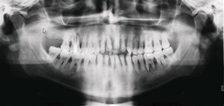

Fig 5. Placement of tilted

implants in existing native bone enables expedited therapy in the case of terminal dentitions.

Fig 5: Representative scenario involving advanced generalized periodontitis with marked bone

loss. Immediate placement (and loading) requires primary stability that cannot be achieved in the

residual tooth sockets of such cases. Alveolectomy and tilted implant placement in the residual

native bone is one approach to immediate implant therapy. In such cases, there is often insufficient

bone volume in zone 3 for implant placement. Fig 6: Panoramic radiographic evaluation following

final prosthesis delivery illustrates the use of tilted implants in zone 2, which was required

to achieve anterior-posterior distribution of implants to support molar function and permit the

intervening period of immediate provisionalization.

Figure 5